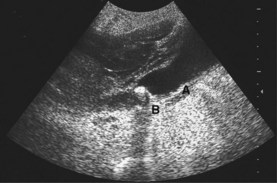

Fig. 8.30 Ultrasound scan showing thick-walled gallbladder (A) containing gallstones with posterior acoustic shadowing (B).